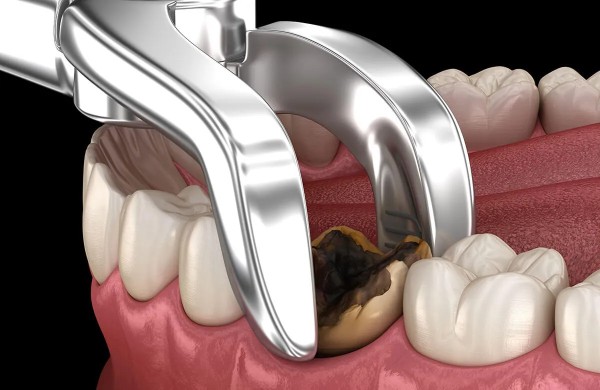

- Sử dụng kìm nha khoa chuyên dụng: Đây là kỹ thuật truyền thống nhưng đòi hỏi bác sĩ phải có kinh nghiệm dày dặn. Bác sĩ sử dụng mỏ kìm để kẹp chặt thân răng, sau đó dùng lực xoay và lay nhẹ nhàng để làm đứt dây chằng quanh răng, giúp lấy răng ra khỏi xương ổ răng một cách dứt khoát.

- Bước 3: Tiến hành nhổ răng: Tùy vào độ khó, bác sĩ sẽ sử dụng các dụng cụ như kìm, bẩy hoặc công nghệ sóng siêu âm Piezotome để tách nướu và đưa răng ra ngoài một cách nhẹ nhàng nhất.